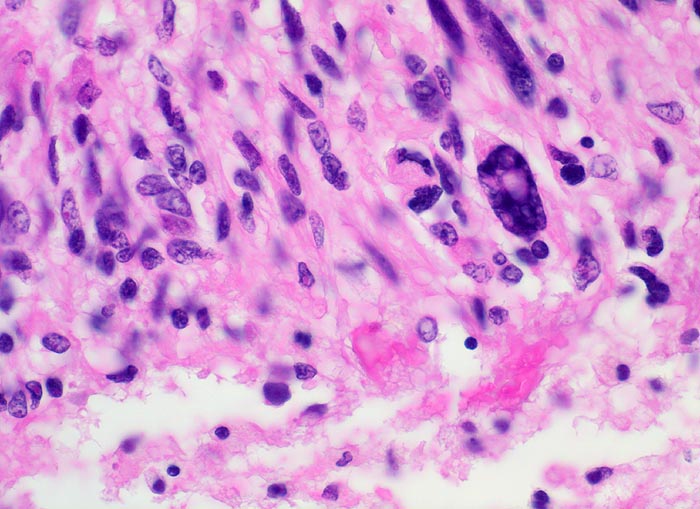

Ein Glioblastom liegt vor, wenn mindestens 3 der folgenden 4 histologischen Kriterien erfüllt sind: Kernatypien (Hyperchromasie und/oder Form- und Grössenvariabilität), Mitosen, Endothelproliferation (Gefässlumina von mehr als einer Lage Endothelzellen umgeben) und flächenhafte oder girlandenartig angeordnete Nekrosen. Ein Teil der Glioblastome entwickelt sich sekundär aus diffusen Astrozytomen Grad II. Bei den übrigen handelt es sich um sogenannt "de novo" entstandene Glioblastome.

Morphologische Merkmale:

• Typische streifenförmige Nekrosen mit randständiger Palisadierung der Tumorzellen.

• Im Zentrum der Nekrose thrombosierte Gefässe umgeben von einem Saum vitaler Tumorzellen.

• Ausgeprägte Zellpolymorphie und Atypie.

• Mitosen.